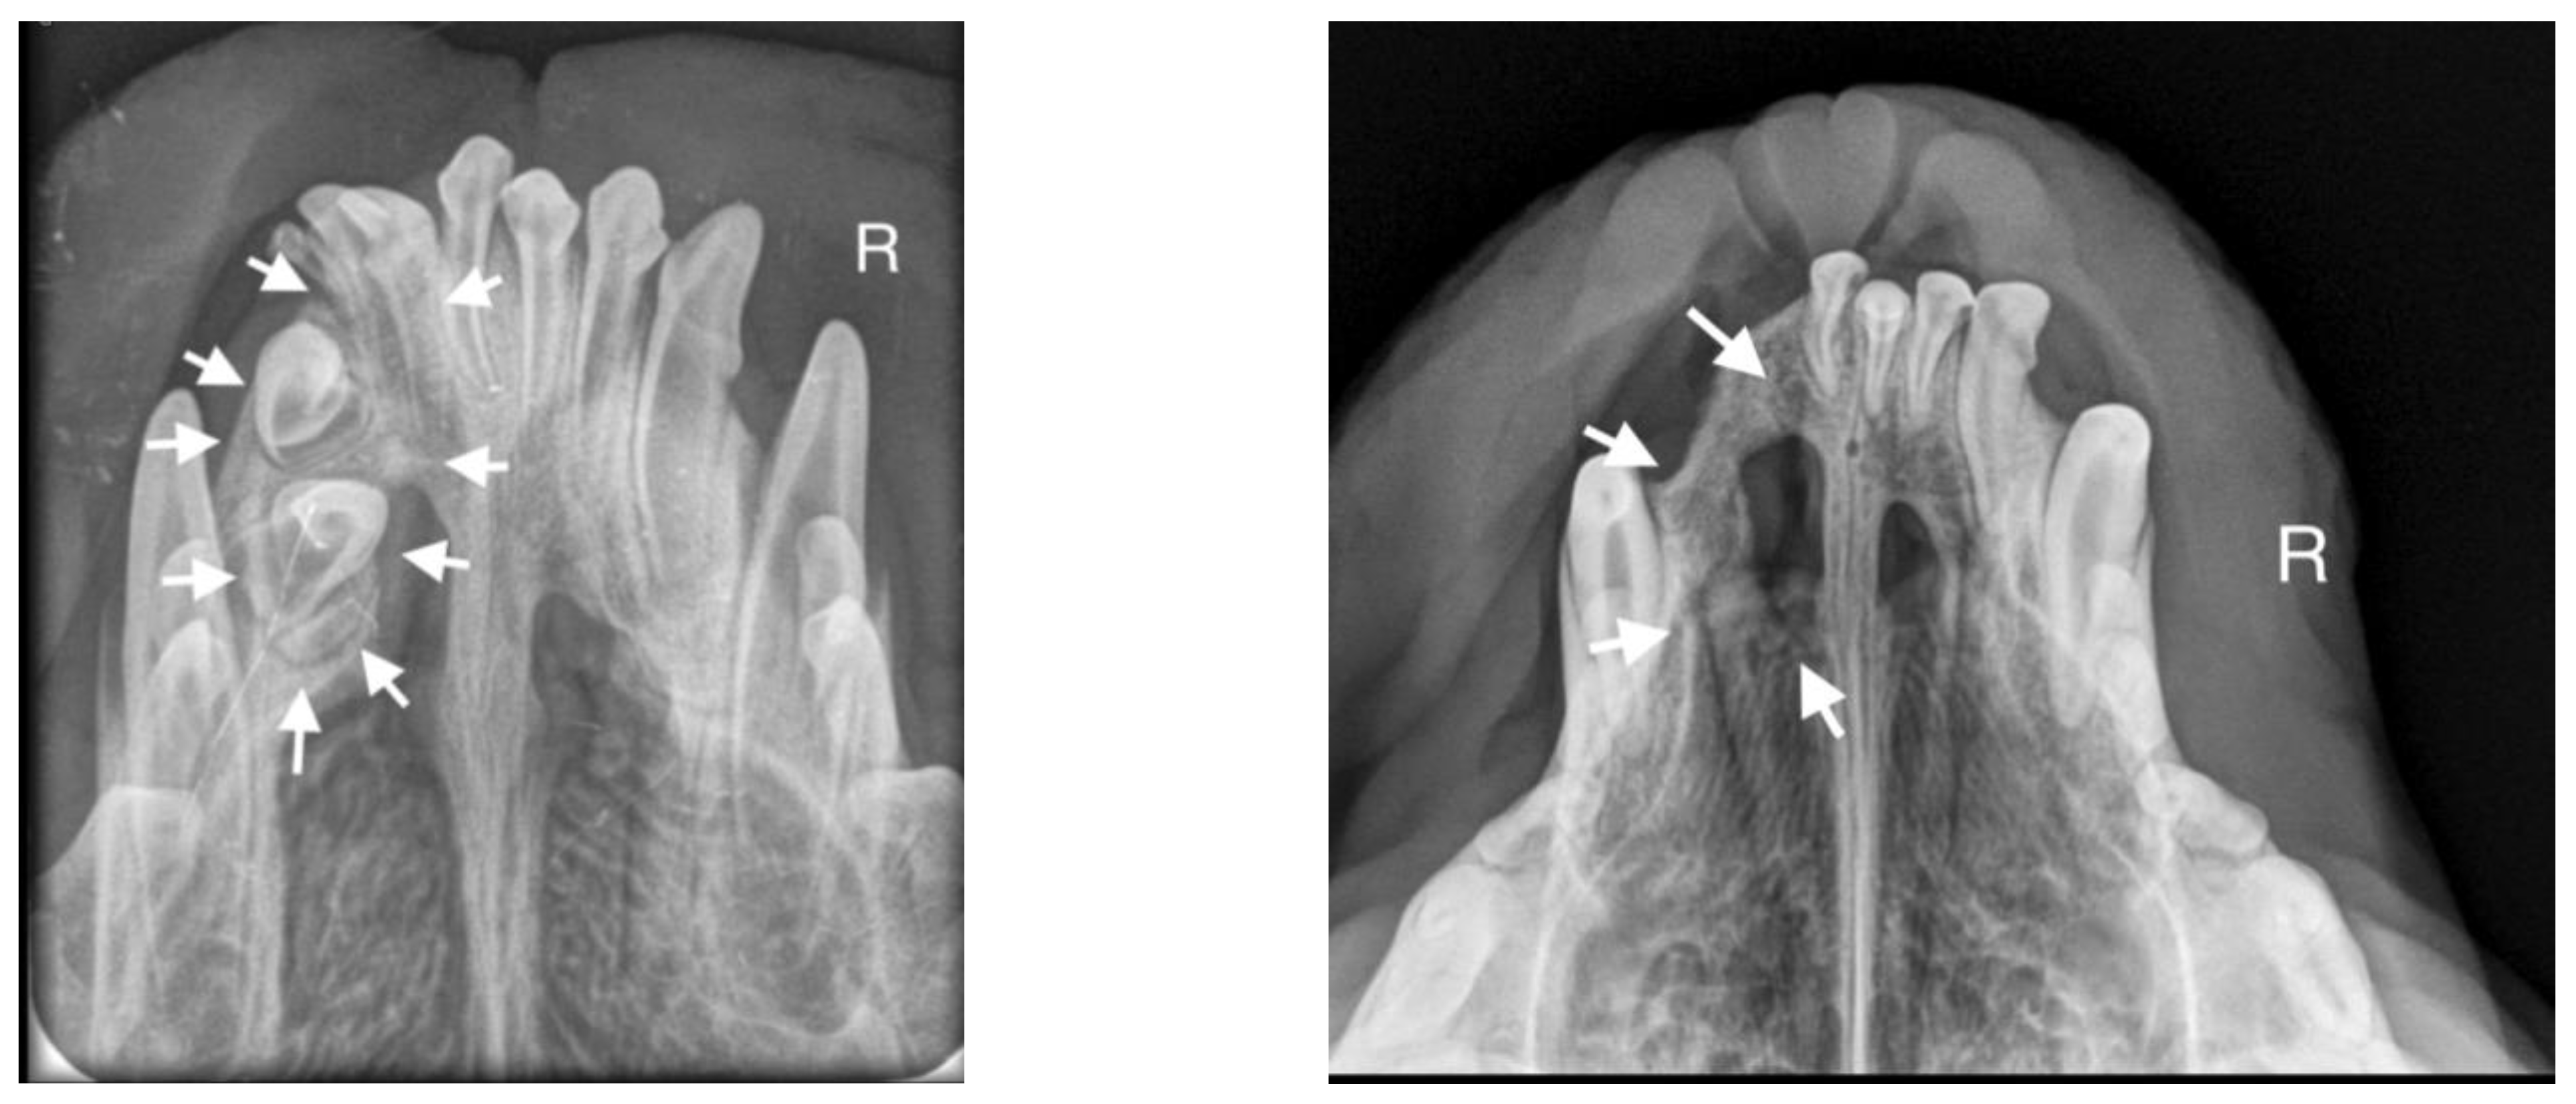

A 10-month-old American Staffordshire Terrier dog was referred for an orthodontic consultation due to abnormal alignment of the maxillary teeth and the resulting bite injuries. Clinical examination revealed three properly aligned incisors on the right side and four incisors (including one tooth with a double crown) on the left side arranged chaotically (Figure 7). Intraoral examination revealed an abnormal palatal crease in the projection of teeth 103–203 and a hard and painful protrusion about 3 cm in diameter on the left side. The roentgenogram showed the presence of three additional incisors, including two unerupted ones, growing in the opposite direction to the alveolar process. The double tooth on the X-ray appeared to be a fused tooth (tooth fusion occurs as a result of physical force or pressure on an adjacent tooth’s bud, leading to the contact of the two tooth buds and their fusion before calcification) [12]. The abnormal growth of the incisors on the left side caused pressure on the incisal bone, along with skewing of the nasal septum to the right side (Figure 8). The third incisor, along with an additional third incisor, showed radiographic features of a dentigerous cyst. A decision was made to perform open extraction of the ectopic teeth using the CLP method.

The bone cavity, after such a large open extraction, was 3.0 cm × 4.2 cm; so, the decision was made to implant polymeric hydroxyapatite with curdlan soaked in 0.9% NaCl into the areas of bone loss. The flap was sutured with 4-0 monofilament single sutures. A follow-up radiograph was taken 28 days after surgery. On clinical examination, the soft tissues were healed properly. On the follow-up radiograph, the bone tissue was healed properly, with new bone formation.

Figure 7. On the left side, the teeth with abnormal eruption are marked with arrows on the X-ray. The right radiograph shows the status 28 days after surgery. Properly formed bone tissue can be seen, with no signs of inflammation or alveolar bone atrophy (marked with arrows).